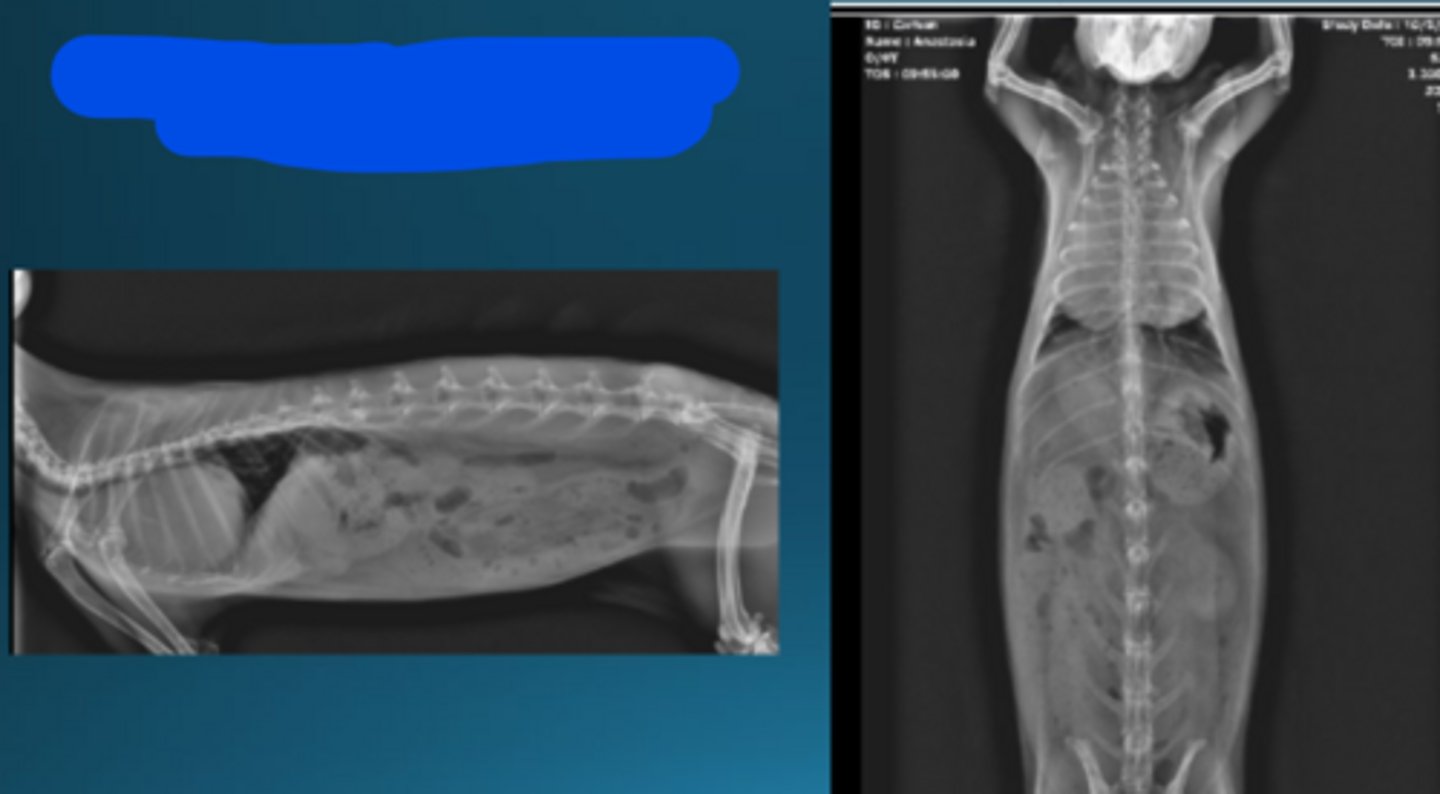

Dorsoventral

What radiographic view is this to image rabbits?

Lateral

Oblique

What radiographic view it this to image rabbits?

To see individual bullae and see dental pathology

Why would you take oblique radiographs in rabbits?

CT

What type of imaging is this in rabbits to see dental disease?